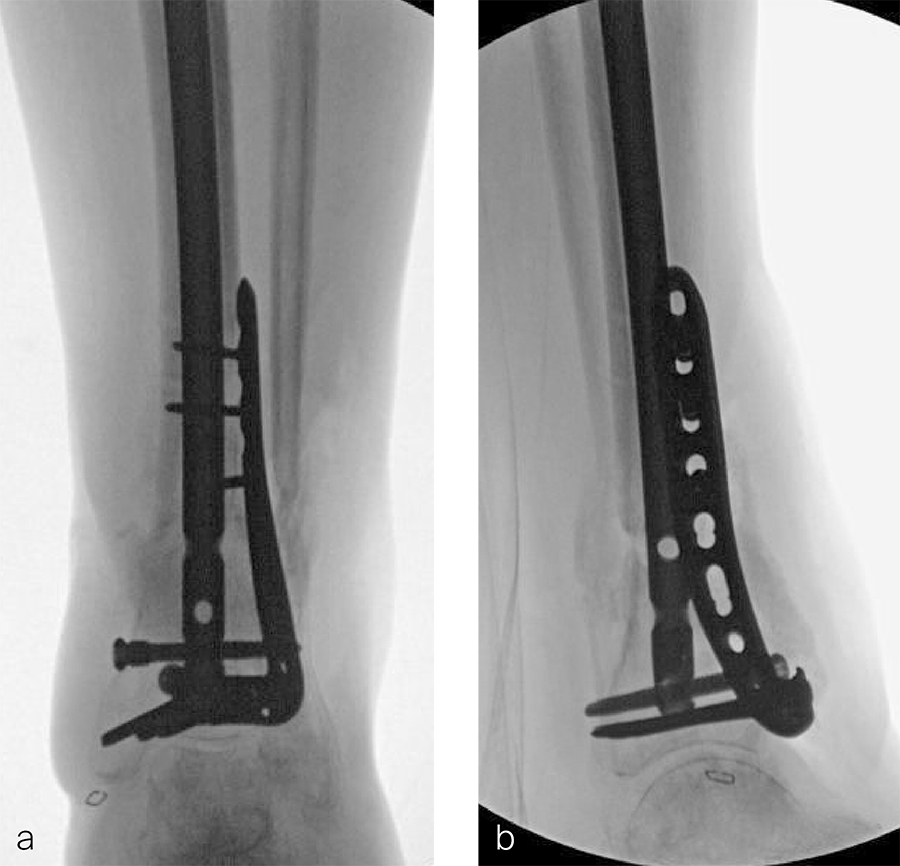

Two months later, the patient had a staged cement spacer removal and hardware removal followed by a new spacer placement (Fig 4). When microbiological cultures were negative for 5 days he was taken to the OR for definitive fixation and bone grafting. RIA bone graft from the ipsilateral femur was taken, a new anterior lateral plate was placed with an adjunct IM nail (and angle stable screws) as the distal plafond was now one articular block (Fig 5).